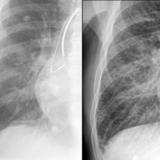

IPE 3 before

Date: 11/05/2005

Views: 2574

IPE 3 after

Views: 2378